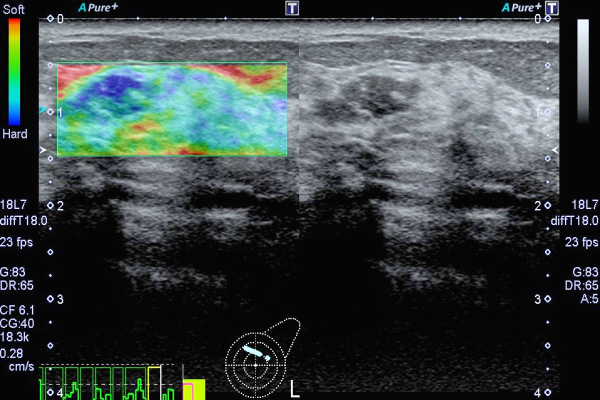

乳腺・甲状腺、体表超音波検査では18~24MHzの高周波プローブを用いることで、詳細な検査画像を得ることができます。また、エラストグラフィは、乳腺や甲状腺などの腫瘤の硬さを評価することができ、良悪性判断の一助となります。見つかった腫瘤に対し精密検査(病理学的検査)を行う為の、エコーガイド下生検(超音波画像で確認しながら身体に針を刺し、腫瘤まで到達させて腫瘤の細胞を直接採取します)も超音波検査室にて行われる場合があります。

乳腺エラストグラフィ